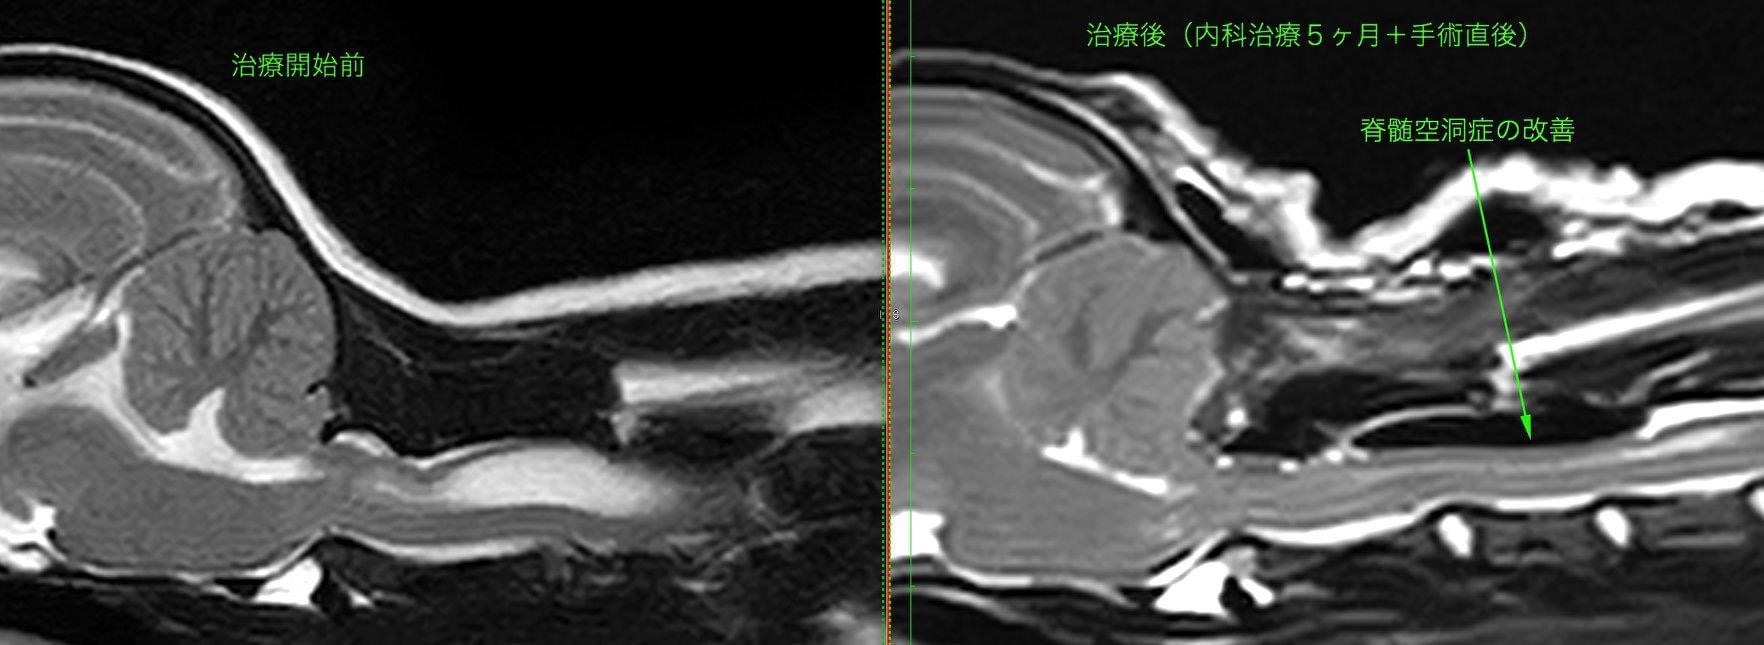

術前と術後のMRI所見(Sagital) 頸部脊髄空洞症の改善が認められました。